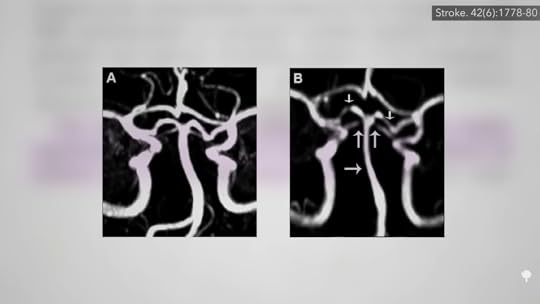

There have been case reports of artery damage due to the “vasoconstrictor effect of cannabis,” which has been well documented. One study found cannabis users had a hundred times greater odds of suffering from multifocal intracranial stenosis, where the arteries inside our brain clamp down at multiple points, as you can see below and at 0:39 in my video Does Marijuana Cause Strokes and Heart Attacks?, but that’s a rare condition. What about strokes?